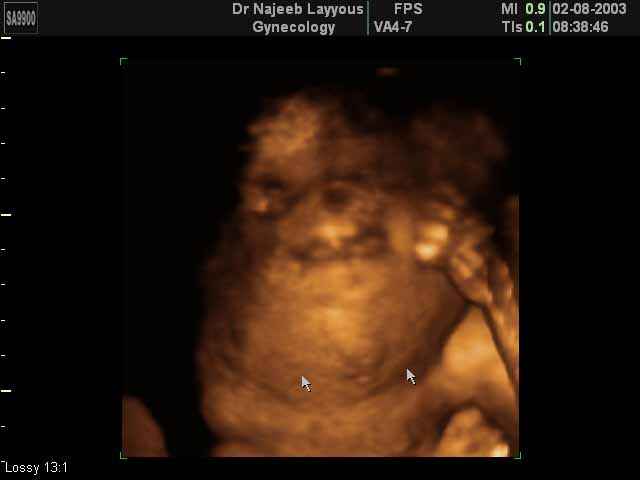

- صور لوجه الجنين في داخل الرحم

- صور جانبية لرأس الجنين